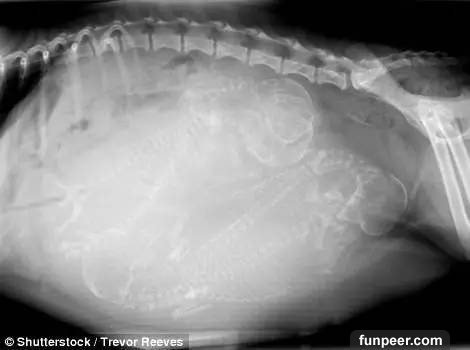

之前發過一部分動物懷孕後拍攝的X光照,最近照片又更新了,繼續來感受下: 這是一隻狗媽媽,數一下似乎是懷了七隻小狗

這兩張也是懷孕狗狗的X光照片